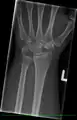

X-ray on the right wrist showing arthrodesis.

X-Ray on Left Hand Post-Proximal Row Carpectomy, in Traction.

X-Ray on Left Hand Post-Proximal Row Carpectomy.